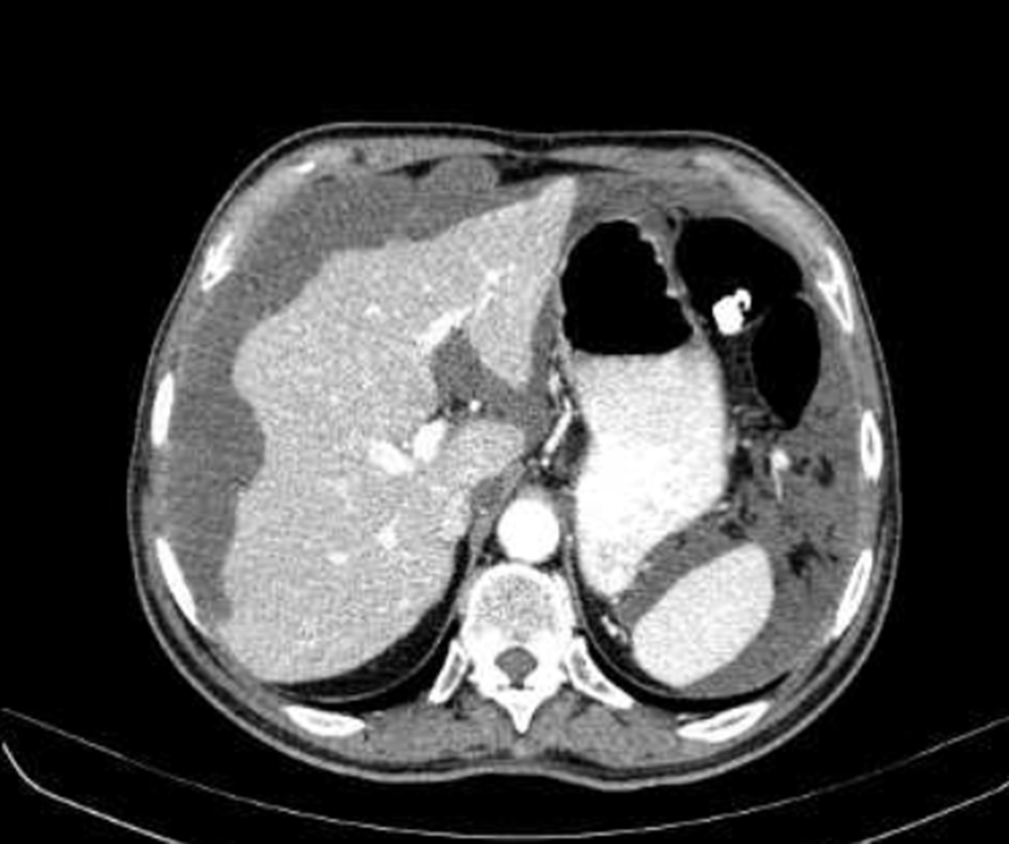

Un paziente di 50 anni si presenta con un quadro di dolore addominale, nausea e progressivo aumento di volume dell’addome. La TC addominale con contrasto mostra la presenza di una massa appendicolare. Questo è il rilievo in addome superiore.

Cosa si evince?

- Quadro normale

- Versamento periepatico

- Scalloping della superficie epatica

- Lacerazione epatica

- Versamento pleurico

Il termine scalloping (Risposta esatta: C) si riferisce a un aspetto caratteristico del fegato osservato durante l’ecografia o la TC, dove i bordi del fegato sembrano avere un profilo ondulato a causa della pressione di un processo lesivo esterno, come nel caso del pseudomyxoma peritonei. Questa condizione è una malattia rara in cui cisti di muco si accumulano nella cavità addominale, causando compressione e alterazioni morfologiche degli organi vicini, come il fegato. Il fenomeno di scalloping del fegato riflette la compressione della caps